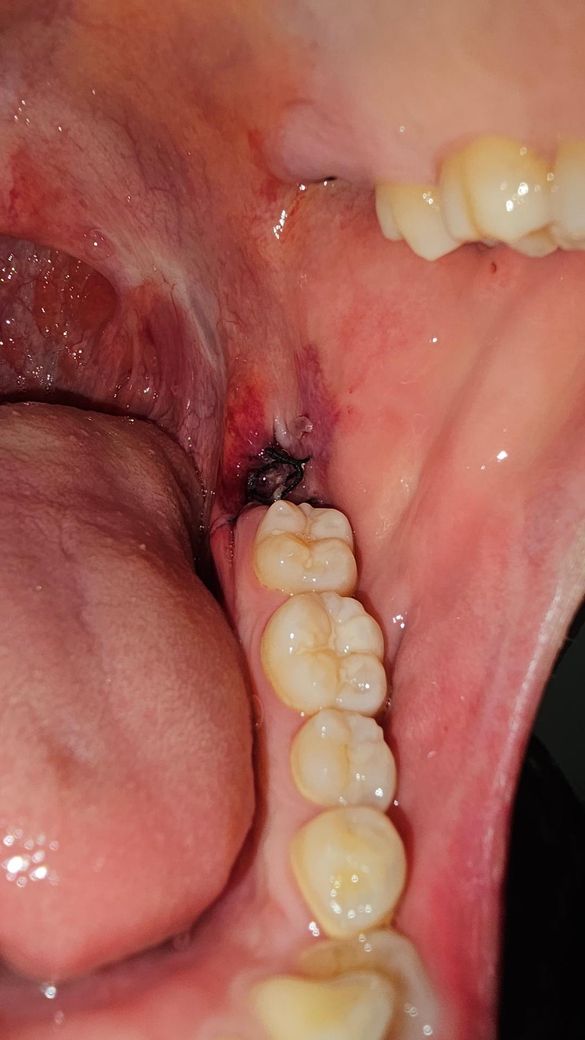

매복사랑니 발치 3일차인데 하얀색 점같은게있어요

안뇽하세요 매복사랑니 발치한지 3일차인데 아랫쪽에 뭔가 하얀색 점같은게 생겼는데 이거 음식물 찌거기인가요? 정상적으로 치유되고있는건가요?

• 2번 째 사진

사랑니 발치한곳 잇몸이 다 아물지 않아서 그럴수 있습니다.사진상으로 문제가 잇어 보이진 않습니다.

사랑니를 발치하고 나면 발치한 부위에 가피등이 형성될수 잇습니다. 사진으로 봤을 경우에는 크게 문제가 없는것으로 보이기 때문에 너무 걱정하지 않으셔도 될것으로 생각됩니다.

1. 사랑니 발치 부위 옆의 볼쪽은 마취주사로 인한 것, 발치 중 기구에 눌려서 그런 것 같고요.

2. 발치 부위의 하얀색 점처럼 생긴 것은 단순 이물질 같습니다. 살살 가글해서 위생관리 해주세요.